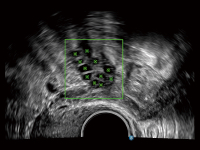

提供解剖示意圖、標(biāo)準(zhǔn)超聲圖像、掃查手法圖和操作者實(shí)時(shí)檢查圖像,指導(dǎo)操作者進(jìn)行標(biāo)準(zhǔn)切面的正確掃查。